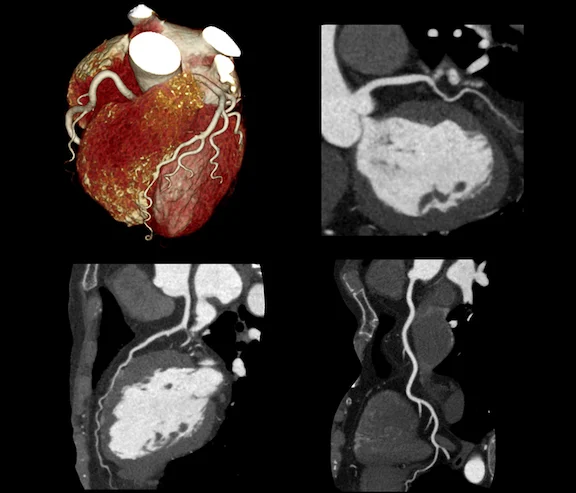

فحوصات القلب والأوعية الدموية (Cardiology Imaging)

تُعد فحوصات القلب من الخدمات الحساسة التي نوليها اهتماماً خاصاً، وتشمل:

- رسم القلب (ECG).

- موجات صوتية على القلب (إيكو – Echo) للكبار والأطفال.

- خدمة هولتر (Holter) لمتابعة نبضات القلب لمدة 24 أو 48 ساعة.